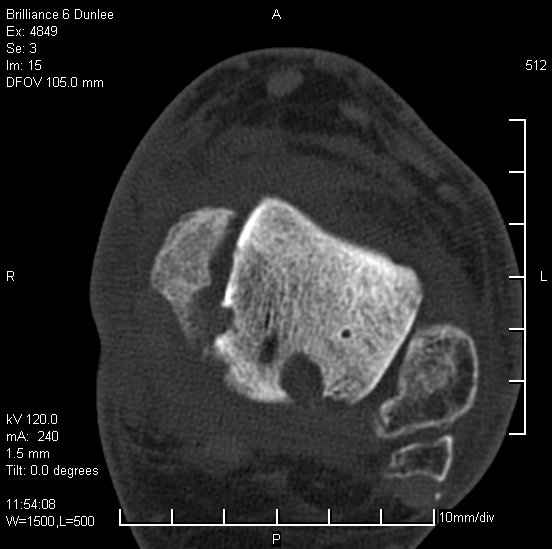

На лечении находится пациент 35 лет. Травма в сентябре 2008 г.- открытый вывих таранной кости

В день травмы ПХО, вправление вывиха, трансартикулярная фиксация. Рана зажила первично. С января нагрузка на конечность. С конца апреля- болевой синдром. На рентгенограммах и КТ признаки ас. некроза таранной кости, артроз подтаранного и голеностопного суставов.

У больного тотальный ас. некрох блока таранной кости, заинтересованы голеностопный и подтараный суставы. Эндопротезирование маловероятно на некротизированную кость. Изолированный подтаранный артродез таран не спасет.При артродезе всю некротизированную кость придется убрать.А далее замещение либо за счет большеберцовой кости, или удлинение на регенерате.